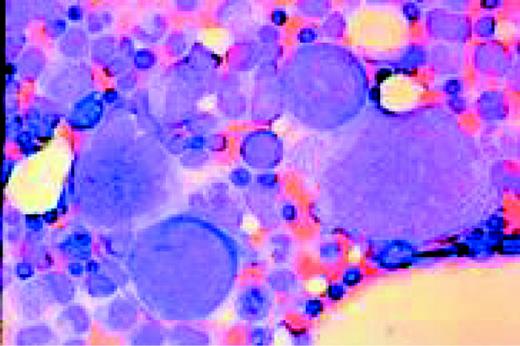

Slide MG1

M7 Acute non-lymphoblastic leukemia (M7) (Acute megakaryocytic leukemia). This high-oil magnification view of a bone marrow aspirate shows the large blasts characteristic of this disease.FIG83